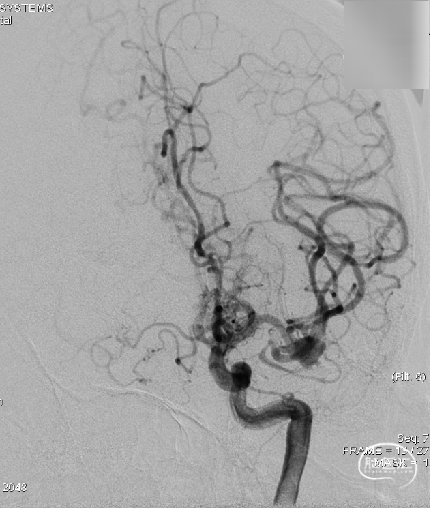

术后影像

复查标准正侧位造影, ICA、MCA、ACA主干及远端分支良好,动脉瘤栓塞满意。

术后工作位+侧位造影

术后三维重建,支架贴壁良好,动脉瘤完全栓塞。